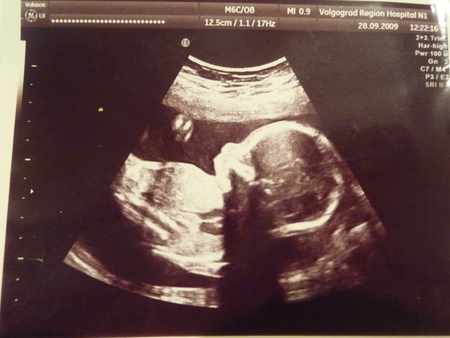

И последнее фото было сделано на сроке 23 недельки, он уже весь не поместился на фото,

Тут он был уже 12 см, уже большенький.